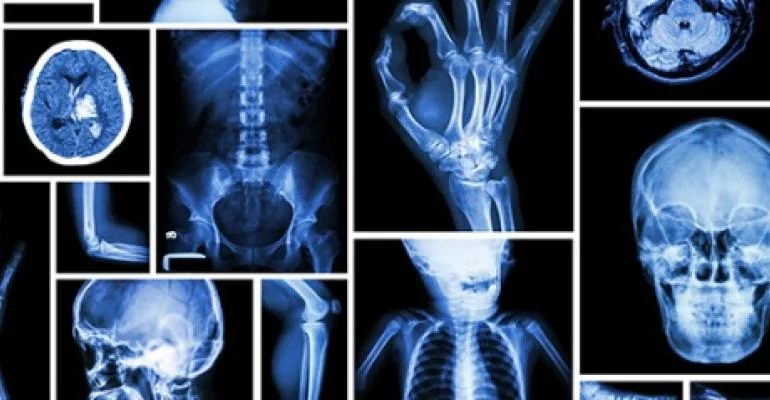

IRMDZ est un Centre de radiologie médicale dédié à fournir des soins exceptionnels à nos patients. Les radiologues d’IRMDZ fournissent des services d'imagerie diagnostique et interventionnelle depuis plus de 40 ans et ont exercé pendant plus d’une décennie à l’international.

Diplômés et spécialisés dans tous les domaines de la radiologie, nos médecins sont en mesure de vous fournir le plus haut niveau de soins. C’est pourquoi tous les équipements de pointe d’IRMDZ sont assistés par Intelligence Artificielle (IA) et sont parmi les plus avancés en matière d’Imagerie Médicale.

Les radiologues d'IRMDZ sont spécialisés dans les techniques de pointe de l'imagerie médicale moderne avec une longue expérience avérée en neuroradiologie mais aussi en imagerie de la femme.

Regroupant l’entièreté des spécialités et sur-spécialités de l’imagerie médicale moderne, IRMDZ propose une offre de soin alliant des plateaux techniques de pointe et des compétences médicales sur-spécialisées.